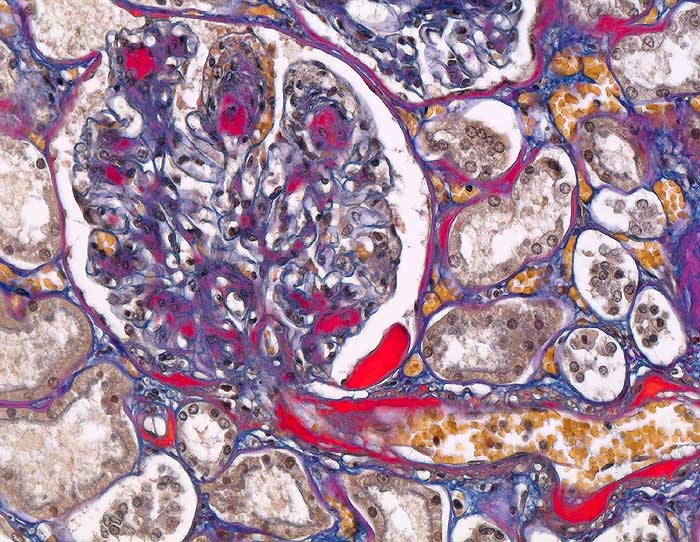

Morphologische Merkmale:

• Verbreiterung des Mesangiums mit Ausbildung von Knoten(noduläre Glomerulosklerose).

• Exsudative Läsionen: Hyaline Schlingenkappen (Proteinthromben in Glomerulumschlingen, im virtuellen Präparat nicht sichtbar) und Kapseltropfen (Proteinablagerungen im Bowman’schen Kapselraum).

• Arteriolosklerose von Vas afferens und efferens (Gefässwandhyalinose durch Ablagerung von Plasmaproteinen und Lipiden in der Gefässwand).

• Intrarenale Atherosklerose.

• Verdickte Basalmembranen der peritubulären Kapillaren.

• Verbreiterung der tubulären Basalmembran.

• Tubulusatrophie mit interstitieller Fibrose und Begleitentzündung.

Im allgemeinen ist die Niere infolge von Glomerulumhypertrophie und Tubulushyperplasie vergrössert und derb, die Oberfläche ist granuliert. Bei schwerer Atherosklerose und fortgeschrittener Niereninsuffizienz kann die Niere auch normal gross oder verkleinert sein. Die Kombination von nodulärer Glomerulosklerose, hyalinen Schlingenkappen (=Proteinthromben in den Glomerulumschlingen (> 1916)) oder Kapseltropfen (> 1907) und Arteriolosklerose in Vas afferens und efferens ist beweisend für eine diabetische Nephropathie. Jede einzelne Läsion für sich genommen ist aber unspezifisch. Eine noduläre Glomerulosklerose kann auch vorkommen bei membranoproliferativer Glomerulonephritis (> 2652), Leichtkettenglomerulopathie oder Amyloidose (> 2019). Der nodulären Glomerulosklerose geht bei Diabetikern eine diffuse Glomerulosklerose (> 1906) voraus. Dabei zeigen die glomerulären Basalmembranen und das Mesangium eine progrediente gleichförmige Verbreiterung. Bei der nodulären und diffusen Glomerulosklerose handelt es sich aber wahrscheinlich um zwei pathogenetisch unterschiedliche, sich überlagernde Krankheitsbilder. Typisch bei Diabetikern ist im Unterschied zur arteriellen Hypertonie die Arteriolosklerose von Vas afferens und efferens (> 1911) und oft auch der Vasa recta. Intrarenale Arterien können eine Atherosklerose mit Atheromen zeigen. Subendotheliale Proteinablagerungen teilweise mit Verschluss der Glomerulumschlingen (Schlingenkappen) und knotige Proteinablagerungen in der Bowman'schen Kapselbasalmebran (Kapseltropfen) gehören zu den sogenannten exsudativen Läsionen (> 1919) (> 1920) der diabetischen Nephropathie und führen zu Synechien sowie zur globalen Glomerulosklerose. Gleichzeitig mit den Glomerulumveränderungen treten tubuläre Basalmembranverbreiterungen auf, später eine Tubulusatrophie und interstitielle Fibrose mit Begleitentzündung. Auch die Basalmembranen der peritubulären Kapillaren sind verdickt.